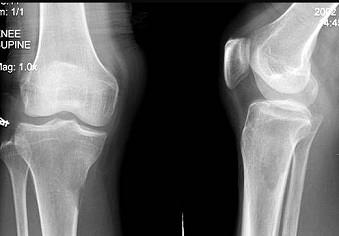

问题 男,59岁,右小腿近端疼痛一年,活动障碍半年,有前列腺癌病史,请结合所提供图像,选择最佳答案 ( )

选项 A、骨肉瘤 B、纤维肉瘤 C、右胫骨骨转移 D、软骨肉瘤 E、右胫骨结核

答案 C